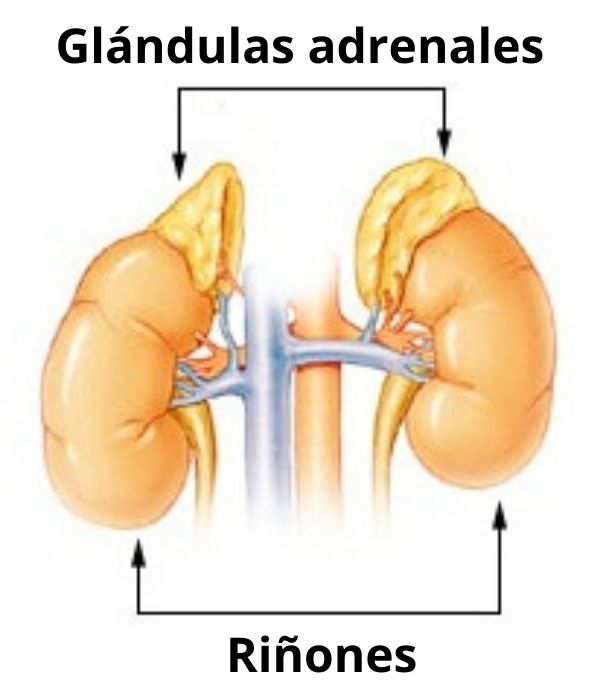

– Las glándulas suprarrenales se encuentran en el polo superior de los riñones y producen hormonas esteroideas y catecolaminas.

Las patologías más representativas corresponden a aquellas que afectan las glándulas endocrinas, entre las que destacan particularmente la diabetes, la osteoporosis, el cáncer de tiroides, el hipo- y el hipertiroidismo, la obesidad, la deficiencia de hormona de crecimiento, la hiper- y la hipoglucemia, los niveles bajos de testosterona, la menopausia, etc.

También están la enfermedad de Addison (lesiones en las glándulas suprarrenales), el síndrome de Cushing (por excesiva producción de cortisol en las glándulas suprarrenales) y la enfermedad de Grave (relacionada con un aumento en la actividad de la glándula tiroides).